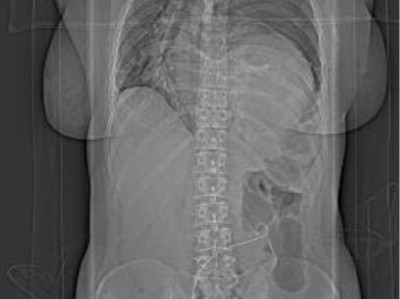

Ein Abstrich vom Gebärmutterhals wird auf ein Objektivträger geschmiert/© Tatiana Buzmakova / Getty Images / iStock (Symbolbild mit Fotomodellen), MRT des Beckens: Uterus und Ovarialtumoren/© Hosten AK et al. / all rights reserved Springer Medizin Verlag GmbH, Ultraschall eines Adnextumors/© Markus Hoopmann, Mehrere Personen erhalten Chemotherapie/© FatCamera / Getty Images / iStock (Symbolbild mit Fotomodellen), Subtypen des epithelialen Ovarialkarzinoms/© Springer Medizin, Frau mit Kopftuch und Infusion/© FatCamera / Getty Images / iStock (Symbolbild mit Fotomodell), Gewinner des Galenus-von-Pergamon-Preises 2025 in der Kategorie Specialist Care/© Marc-Steffen Unger, Frau bereitet einen Smoothie zu/© Tijana Simic / Getty Images / iStock (Symbolbild mit Fotomodell), Subkutane Injektion/© myskin / stock.adobe.com (Symbolbild mit Fotomodel), Eine ältere Frau bekommt eine intravenöse Therapie/© peopleimages.com / stock.adobe.com, Ärztin betrachtet Mammografie-Befund/© Gorodenkoff / stock.adobe.com (Symbolbild mit Fotomodellen), Frau bei Mammografie-Untersuchung/© Myroslava / Stock.adobe.com (Symbolbild mit Fotomodellen), Frau setzt sich ein Pflaster auf den Schenkel/© svetikd / Getty Images / iStock (Symbolbild mit Fotomodell), Lungenmetastasendiagnostik/© Krämer S. et al. / all rights reserved Springer Medizin Verlag GmbH, Verlagerung von Oberbauchorganen in den Thorax/© Koop H (Mit freundl. Genehmigung der Radiologischen Abteilung), Multiple Papeln auf der Hand bei chronischer Prurigo/© E. Steffens et al. doi.org/10.1007/s00105-023-05131-8 unter CC-BY 4.0, Hysterektomie/© nkeskin / Getty Images / iStock, Search Icon, Person setzt DNS-Probe in Maschine ein/© Vit Kovalcik / stock.adobe.com, Mann raucht Joint/© Daniel Sierralta / Westend61 / stock.adobe.com (Symbolbild mit Fotomodell), Blut in Toilette/© stylefoto24 / stock.adobe.com